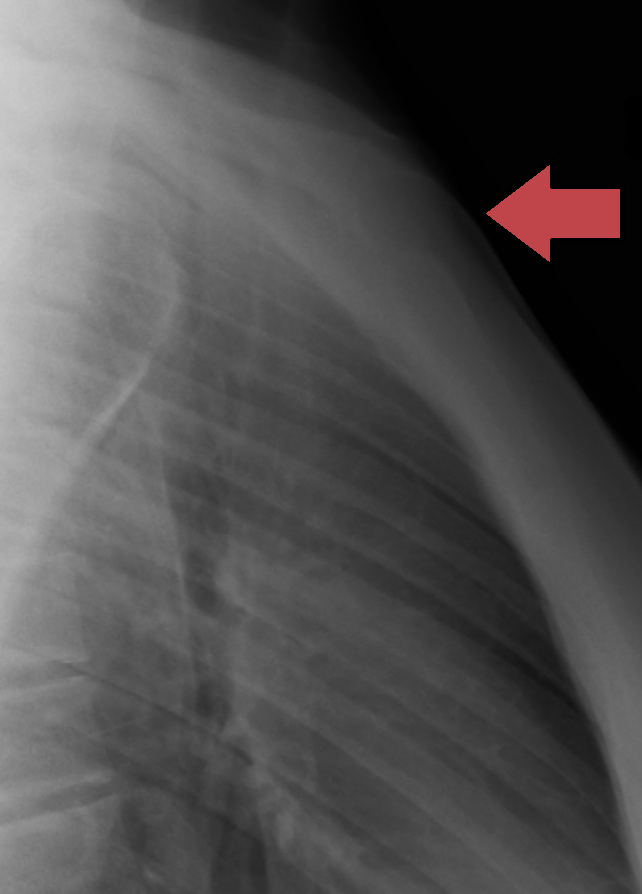

복장뼈는 흉부의 앞면에 있는 길쭉한 편평골이다. 복장뼈 윗부분은 빗장뼈와 관절을 이루며 지지하고, 그 가장자리는 첫 7쌍의 갈비뼈의 갈비연골과 붙어 있다. 복장뼈 안쪽 표면은 복장심장막인대와 연결되어 있고, 가장 윗부분은 목빗근과도 연결되어 있다.

복장뼈는 좁고 납작한 뼈로, 가슴 앞쪽의 중간 부분을 형성한다. 자연스러운 자세에서 복장뼈는 비스듬히 아래쪽과 앞쪽으로 기울어져 있다. 앞쪽은 약간 볼록하고 뒤쪽은 오목하다. 위쪽은 넓고 "T"자 모양이며, 자루가 몸통과 연결되는 지점에서 좁아진 다음, 몸통의 중간 부분 아래까지 다시 약간 넓어지고, 아래쪽 끝으로 갈수록 좁아진다. 성인의 경우 복장뼈는 평균적으로 남성이 여성보다 약 1.7cm 더 길다.

2. 1. 흉골자루

복장뼈자루(manubrium, 라틴어로 '손잡이'라는 뜻)는 복장뼈의 넓고 위쪽 부분이다. 사변형 모양으로 위쪽에서 좁아지며, 4개의 경계를 갖는다. 위가슴패임(목패임)은 복장뼈자루의 가장 넓은 부분인 위쪽 중앙에 위치한다. 이 패임은 양쪽의 빗장뼈 사이에서 만져볼 수 있다. 이 패임의 양쪽에는 오른쪽과 왼쪽의 빗장뼈 패임이 있다.[1]

복장뼈자루는 복장뼈 몸통, 빗장뼈, 그리고 첫 1.5 쌍의 갈비뼈 연골과 연결된다. 아래쪽 경계는 타원형이고 거칠며, 몸통과의 관절 형성을 위해 얇은 연골 층으로 덮여 있다. 가쪽 경계는 각각 위쪽에는 첫 번째 갈비 연골을 위한 우묵한 곳으로, 아래쪽에는 작은 면으로 표시되어 있으며, 몸통의 위쪽 각도에 있는 유사한 면과 함께 두 번째 갈비뼈의 갈비 연골을 수용하기 위한 패임을 형성한다. 첫 번째 갈비 연골을 위한 우묵한 곳과 두 번째 갈비뼈를 위한 반면 사이에는 위에서 아래로 중간을 향해 경사진 좁고 굽은 모서리가 있다. 또한, 위복장심장막 인대는 심낭을 복장뼈자루의 뒤쪽에 부착한다.

2. 2. 흉골몸통

복장뼈 몸통(body) 또는 검상체(gladiolus)는 복장뼈의 가장 긴 부분이다. 편평하며 앞면과 뒷면만 있는 것으로 간주된다. 앞면은 평평하며 위쪽과 앞쪽으로 향해 있으며, 셋째, 넷째, 다섯째 관절와에 마주하는 3개의 가로 능선이 있다. 큰가슴근은 양쪽에 부착된다. 몸통의 세 번째와 네 번째 부분의 접합부에는 크기와 형태가 다양한 구멍인 복장뼈 구멍(sternal foramen)이 가끔 보인다. 약간 안쪽으로 오목한 뒷면에도 앞면의 능선보다 덜 뚜렷하지만 3개의 가로선이 표시되어 있으며, 양쪽의 아래쪽 부분에서 가슴가로근이 시작된다.

복장뼈각은 몸통이 자루뼈에 연결되는 지점에 위치한다. 복장뼈각은 복장뼈가 가장 앞으로 튀어나온 지점에서 느껴질 수 있다. 그러나 어떤 사람들은 복장뼈각이 오목하거나 둥글다. 신체 검사 시 복장뼈각은 두 번째 갈비뼈가 이곳에 부착되기 때문에 유용한 랜드마크이다.[1]

복장뼈 골절은 다소 드물게 발생한다. 자동차 사고 시 운전자의 가슴이 스티어링 칼럼에 부딪히는 것과 같은 외상으로 인해 발생할 수 있다. 복장뼈 골절은 일반적으로 분쇄 골절이다. 복장뼈 골절의 가장 흔한 부위는 복장뼈각이다. 일부 연구에 따르면, 때때로 "가슴뼈 펀치"라고 불리는 복장뼈 부위에 대한 반복적인 펀치나 지속적인 구타 역시 복장뼈 골절을 유발할 수 있다고 한다. 이는 하키나 미식축구와 같은 격투 스포츠에서 발생한 것으로 알려져 있다. 복장뼈 골절은 폐 타박상과 같이, 멍든 폐 조직과 같은 기저 부상과 함께 나타나는 경우가 많다.[11]

흉골 골절 (fracture of the sternum영어, Sternumfrakturde)은 흉곽 골절의 하나이다. 대부분의 경우 직접적인 외력에 의해 발생하며, 골절 부위로는 흉골병, 흉골체의 경계부에 많이 발생한다. 빈도는 높지 않으며, 교통 사고 시 운전자가 핸들로 앞 가슴을 강타하는 등의 경우에 발생할 수 있다.